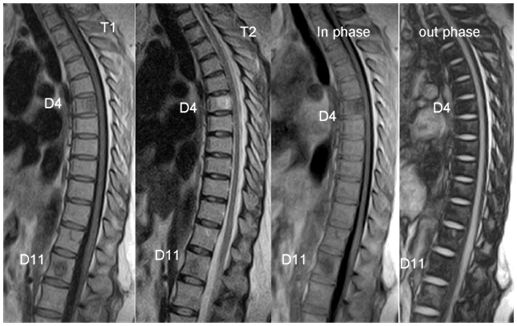

Marrow infiltrative processes, such as malignant neoplasms, tend to replace the fatty marrow components completely. Accordingly, researchers have hypothesized that chemical shift MR imaging might be a useful technique for the evaluation of axial bone marrow lesions. Chemical shift MR imaging can demonstrate the relationship between the amount of fat and water that coexist in the same voxel. Osseous elements, however, will also affect this relationship; thus, the degree of signal intensity change may not be proportional to the quantity of hematopoietic marrow alone. Hemangiomas for example are slowly growing, benign neoplasms that are commonly found in the vertebral bodies. Histopathologically, they consist of thin-walled, blood-filled vessels and sinuses that are lined by endothelium, are interspersed among the bone trabeculae, and have a variable amount of fat. Some, such as those with predominant fat content, do not demonstrate a drop in signal intensity because there are few or no nonlipid elements. However atypical hemangiomas [Figure 3], which contain only small or microscopic quantities of fat, may demonstrate the utility of chemical shift MR imaging because they will lose signal intensity on out-of-phase images.15

Figure 3 Two vertebral hemangiomas at D4, D11 levels (white arrows), the appearance showed signal drop (D4) on out-phase images.